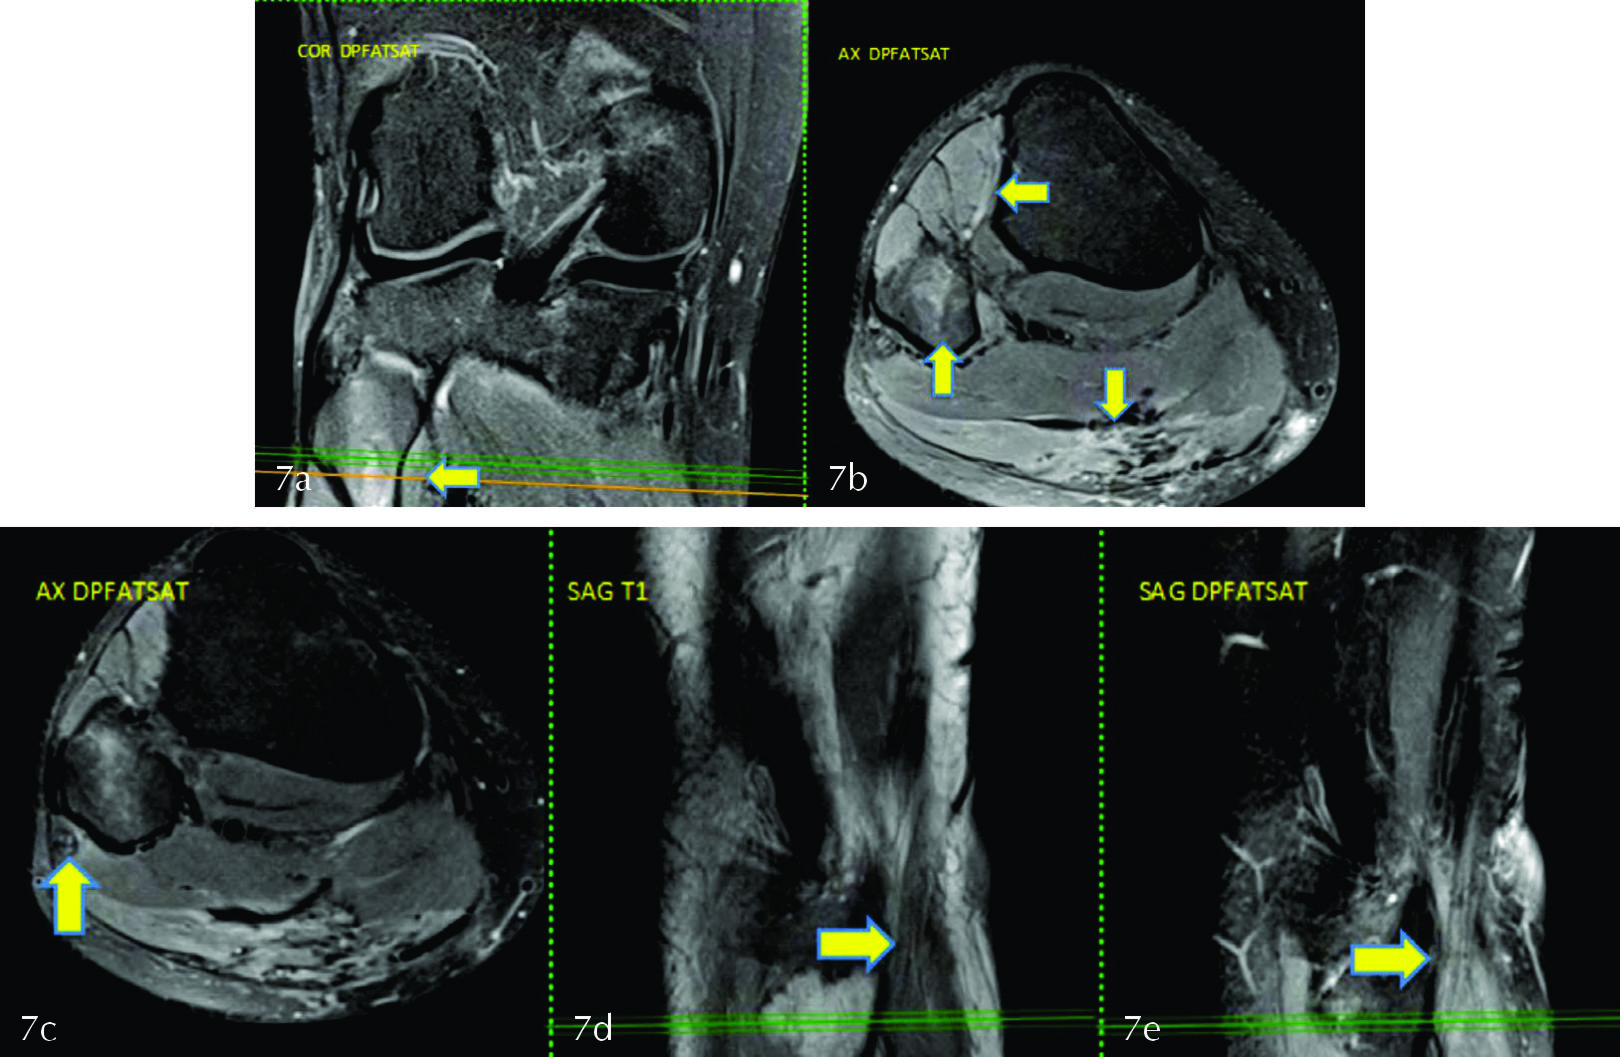

Paciente de 25 años, SM, con antecedente de traumatismo de rodilla, al que se le solicita RM de rodilla derecha con dato clínico de gonalgia.

En la misma se evidencia edema a nivel de los músculos de la logia antero-externa de pierna: tibial anterior, extensor largo de los dedos y peroneo largo (fig. 7 ay b), territorio del nervio peroneo. Se asocia edema subcutáneo y contusión en la cabeza del peroné y músculos gemelos. Estos hallazgos sugieren lesión traumática del nervio peroneo.

En las figuras 7 c, d y f se visualiza el nervio peroneo engrosado con aumento de señal compatible con lesión traumática en el sector topografiado por detrás de la cabeza del peroné. Este tipo de lesión se asocia frecuentemente a fracturas o contusión de peroné como en éste caso.

Figura 7

a) imagen coronal en secuencia DPFATSAT donde se evidencia edema en la cabeza del peroné y gemelos en relación a contusiones. En la imagen axial b) se visualiza edema de la musculatura antero-externa de pierna. c,d,e) se observa el nervio peroneo en los planos axial y sagitales con engrosamiento y aumento de señal (flechas).